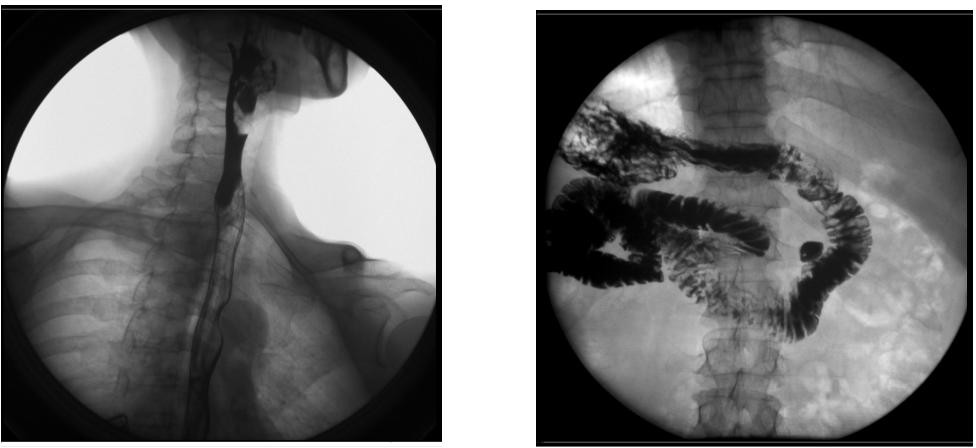

1) 胃肠数字化透视、消化道造影检查,胸部、头颅及全身骨骼普通摄影。

2) 胃肠、食道、脊髓、关节腔、胆道、支气管、静脉、周边血管、泌尿系统、子宫输卵管等数字化造影。

【临床图像】